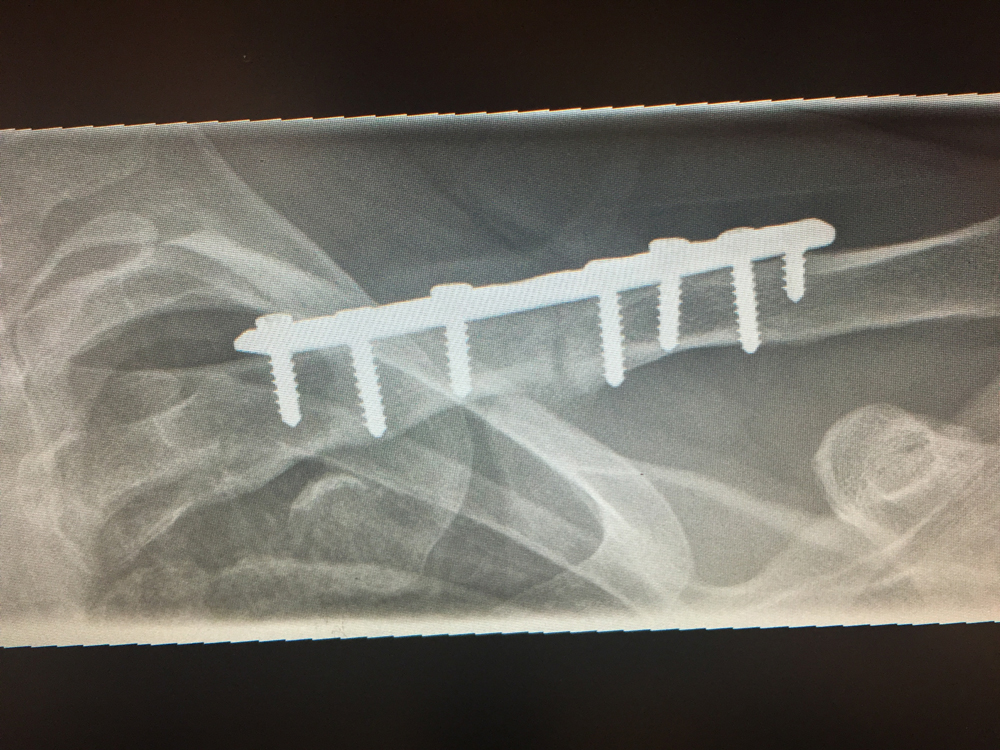

Surgery to realign the fracture is generally for fractures with large displacement, subcutaneous or open fractures and fractures in individuals with high demand of their shoulder ie overhead athletes.

The fracture is typically held reduced by a modern low profile pre-contoured plate. These plates are all palpable under the skin and may cause enough irritation to require removal. Plate removal is done in 10-20% of cases.

Plate removal followed by a return to contact sport is associated with the risk of re-fracture.